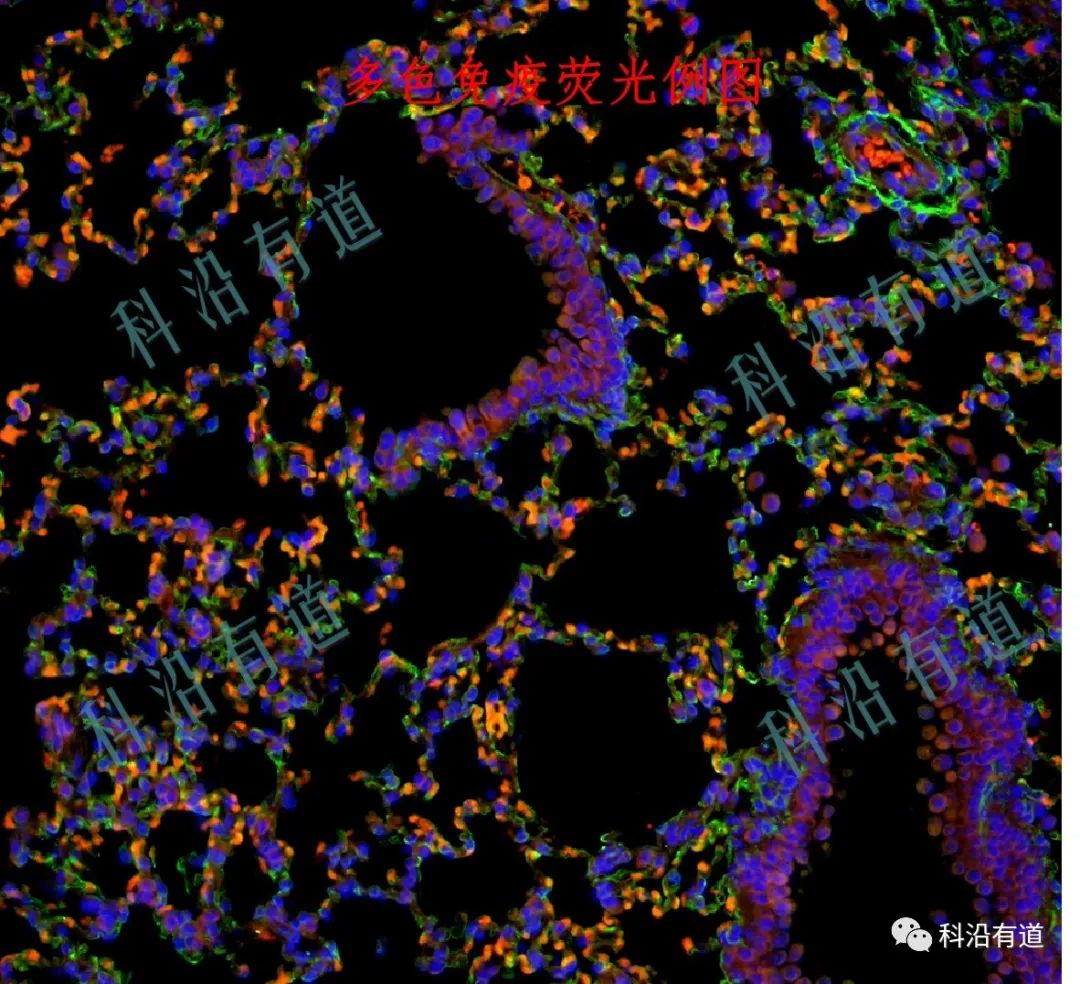

一、TSA多重免疫荧光切片制作:

TSA技术(全称为Tyramide Signal Amplification)利用辣根过氧化酶(HRP)对靶蛋白进行高密度原位标记,提高检测的灵敏度,大幅提高信噪比。TSA信号不受微波法影响,并能在抗体去除后保留信号,TSA是共价键结合,非常稳定。在MWT微波法处理后,可以进行下一轮染色检测,而不必担心上一波染色中抗体的干扰。因此,可以使用同一种属来源的一抗进行多色标记。每一轮染色换用不同荧光标记的TSA,可对石蜡切片样本多重染色。

三、多重免疫荧光切片全景扫描和数据分析:通过全景多色荧光扫描设备,可以对不同抗体标记的荧光通道进行逐个扫描成像,可以覆盖400nm-800nm范围内的光谱信号,最终可以生成融合后的多色荧光图像,利用看图软件可以对每个通道进行浏览观看,也可以对其中某几个通过进行组合观看,还可以对表达的蛋白抗体进行统计计数、距离分析、共表达分析等。